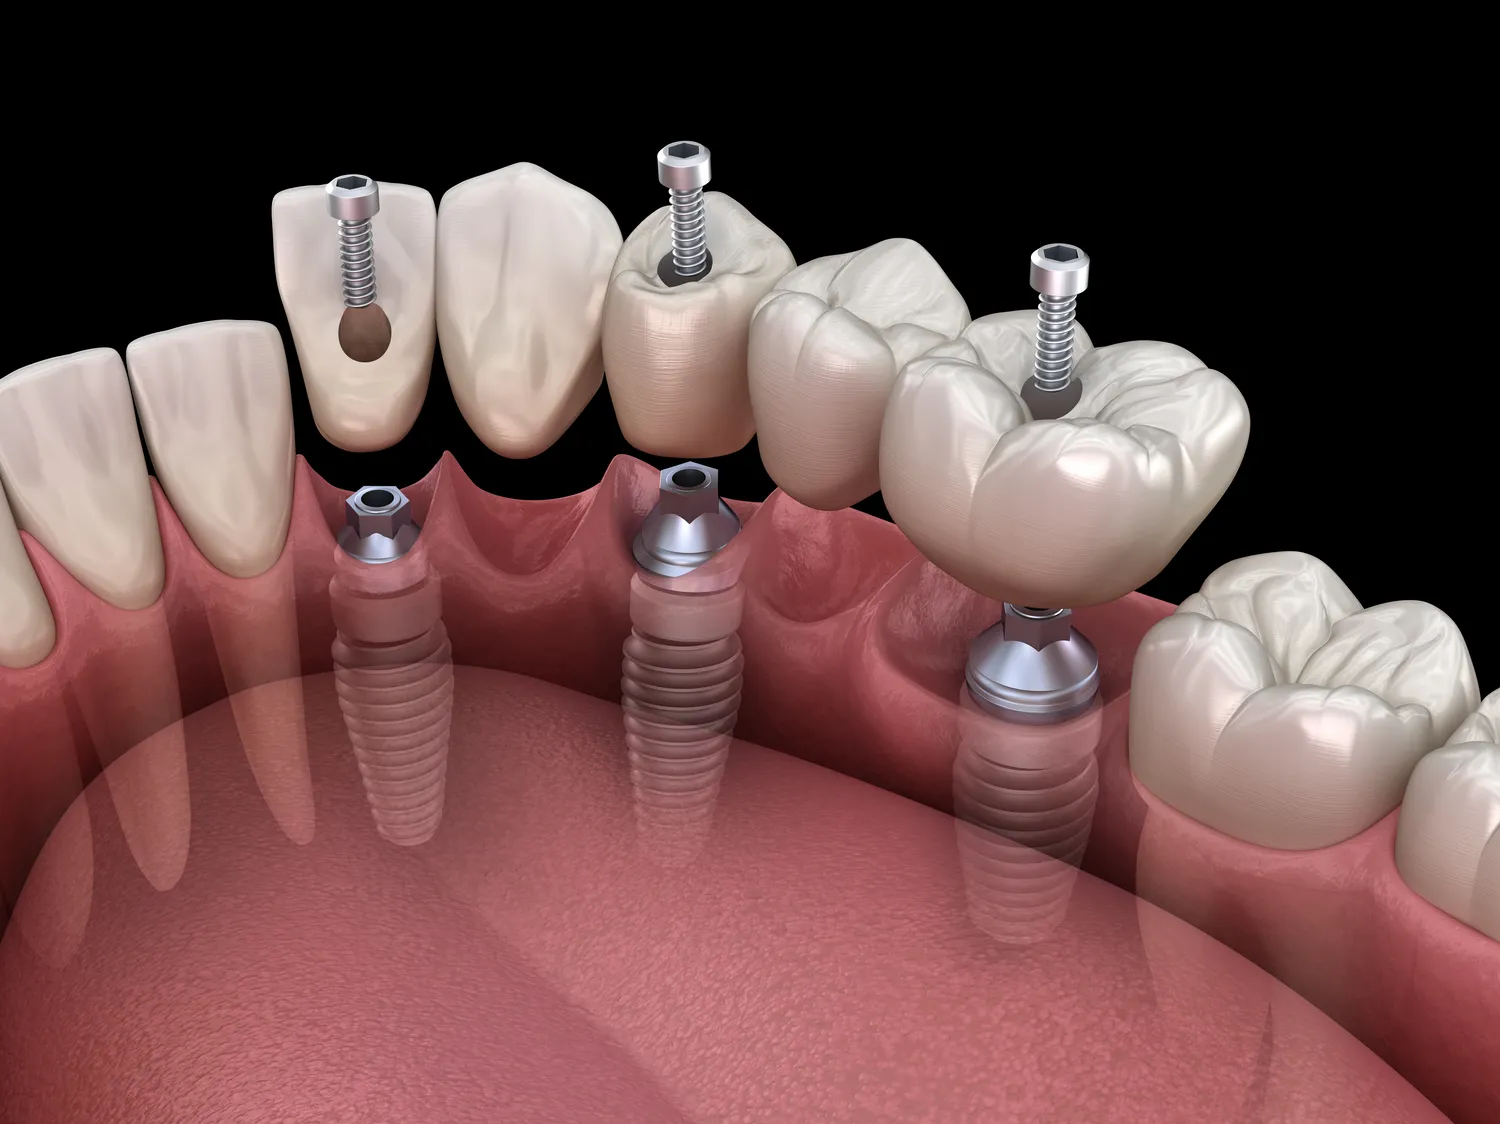

Proces wszczepienia implantów zębowych jest skomplikowany i wymaga kilku etapów, które mogą trwać od kilku miesięcy do nawet roku. Pierwszym krokiem jest dokładna ocena stanu zdrowia pacjenta oraz wykonanie zdjęć rentgenowskich w celu oceny struktury kości. Następnie lekarz podejmuje decyzję o planie leczenia i przystępuje do zabiegu chirurgicznego polegającego na wszczepieniu implantu w kość szczęki. Po tym etapie następuje czas gojenia, który trwa zazwyczaj od 3 do 6 miesięcy. W tym czasie implant integruje się z kością w procesie zwanym osteointegracją. Po zakończeniu tego etapu można przystąpić do wykonania korony protetycznej, która jest umieszczana na implancie. Cały proces może być czasochłonny, jednak warto pamiętać, że każdy etap jest niezbędny dla osiągnięcia optymalnych rezultatów i zapewnienia trwałości implantu.

Decyzja o wymianie implantu zębowego może być trudna i często wiąże się z wieloma pytaniami oraz wątpliwościami. Implanty z reguły są projektowane tak, aby były trwałe i mogły służyć przez długi czas, jednak istnieją sytuacje, w których ich wymiana może być konieczna. Najczęściej wymiana implantu jest wskazana w przypadku wystąpienia poważnych powikłań, takich jak infekcje czy niepowodzenia w integracji implantu z kością. Czasami również zmiany w stanie zdrowia pacjenta mogą wpłynąć na konieczność wymiany implantu. Na przykład choroby ogólnoustrojowe lub problemy ze zdrowiem jamy ustnej mogą prowadzić do osłabienia struktury implantu lub tkanek wokół niego. Ważne jest, aby regularnie konsultować się ze specjalistą i zgłaszać wszelkie niepokojące objawy, takie jak ból czy obrzęk w okolicy implantu.

Jak każda procedura medyczna, wszczepienie implantów zębowych wiąże się z pewnymi ryzykami oraz potencjalnymi powikłaniami. Najczęściej występującym problemem jest infekcja w miejscu wszczepienia implantu. Może to prowadzić do zapalenia tkanek wokół implantu oraz osłabienia jego stabilności. Inne możliwe komplikacje to uszkodzenie nerwów lub naczyń krwionośnych podczas zabiegu chirurgicznego oraz problemy z integracją implantu z kością. W rzadkich przypadkach może wystąpić również reakcja alergiczna na materiały użyte do produkcji implantu. Aby minimalizować ryzyko powikłań, ważne jest przestrzeganie zaleceń lekarza przed i po zabiegu oraz dbanie o higienę jamy ustnej. Regularne kontrole u stomatologa pozwalają na szybkie wykrycie ewentualnych problemów i podjęcie odpowiednich działań w celu ich rozwiązania.